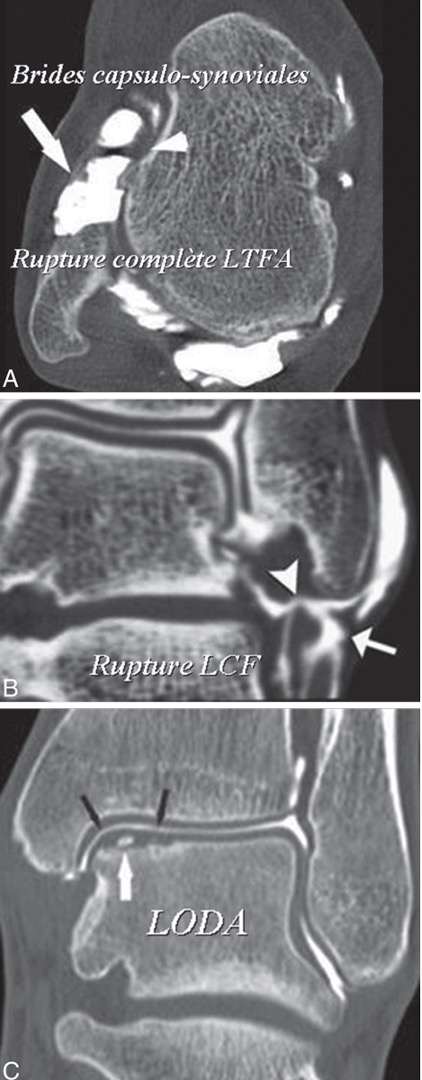

Le bilan d’imagerie permet de confirmer la laxité retrouvée à l’examen clinique.

Il permet aussi d’établir une cartographie précise des lésions ligamentaires et des lésions associées (tendinopathies, conflits osseux, lésions du cartilage).

Plusieurs examens peuvent être proposés : un arthroscanner, une I.R.M, une échographie ou des radiographies dynamiques.